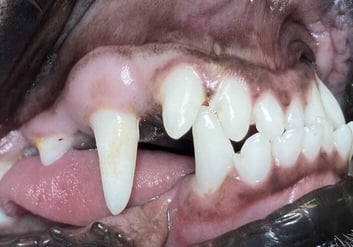

In general, an open extraction technique is advisable for the extraction of the large (especially the permanent) canine tooth. Closed extraction of the canine teeth in young animals can be tempting because the periodontal ligament space is usually wider than in mature patients. Tension-free closure of the site after closed extraction is usually not possible without mobilisation and advancement of the gingiva. Partial closure should be successful to retain the blood clot in the alveolus and support granulation and healing by second intention. Wound breakdown is a possible complication of open extraction techniques, but this can be avoided by appropriate technique ( Figure 1).

The formation of an oronasal fistula after extraction of a maxillary canine tooth or a mandibular fracture during extraction of a mandibular canine tooth remain possibilities, even in young patients. The extraction of deciduous canine or incisor teeth causing trauma to the palate or other soft tissue is the only practical treatment option.

The close proximity of the developing crowns of the permanent teeth is an important consideration. Contact with these structures during the extraction process could cause enamel defects on the permanent canine teeth. It is important to avoid the use of luxators or elevators on the lingual side of the deciduous mandibular canine teeth, and on the mesial aspect of the deciduous maxillary canine, during the extraction procedure.

Radiography is important to confirm the position and degree of resorption of the deciduous teeth to be extracted. Like all deciduous dentition, the tooth roots are extremely long in comparison to the length of the crowns. This is especially dramatic in deciduous canine and incisor teeth: the roots of these teeth could be as much as four to six times the length of the crown. For better visualisation, an open technique is advisable. The complete extraction of the deciduous canines is important in interceptive orthodontic procedures, as retained root remnants could still affect the position of the permanent succedaneous canine teeth. Post-operative radiography to confirm complete extraction in these cases is therefore important.